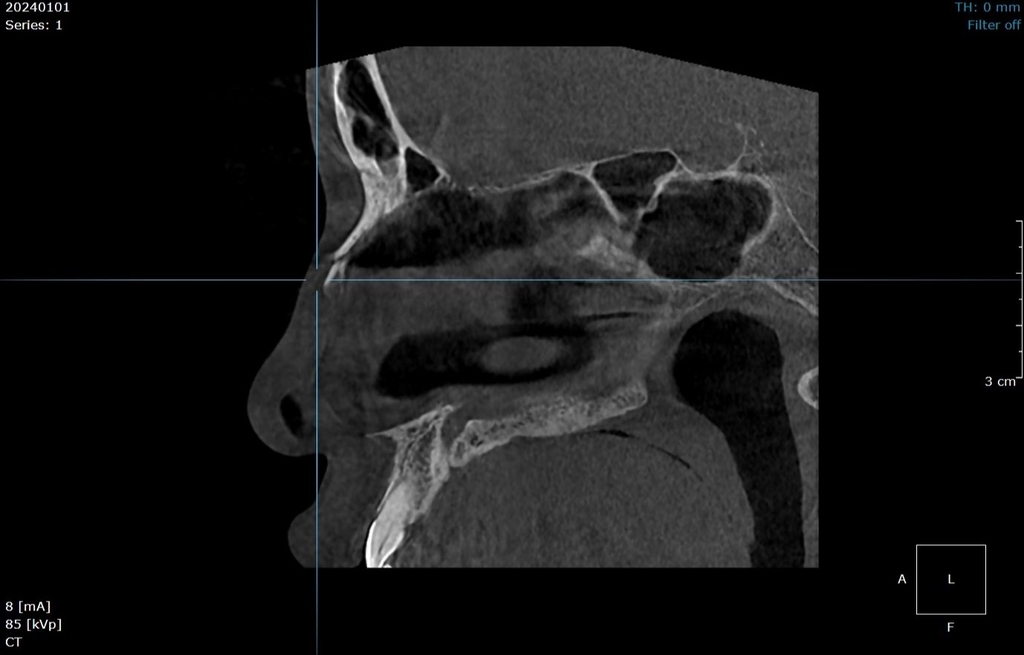

🪻Bệnh nhân bị chấn thương đến thăm khám tại Hồng Hoàng, thông qua hình ảnh chụp CLVT răng hàm mặt dưới đây chẩn đoán bệnh nhân bị gãy xương mũi.

👉 Phát hiện được các tổn thương về xương ở khu vực hàm mặt: gãy xương, rạn xương, u nang...